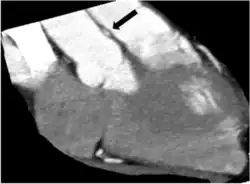

Anomalous origin of a coronary artery from the opposite sinus are relevant on a clinical level due to a significant association with sudden cardiac death, if they are accompanied by intramural course. Indeed, the main feature responsible for adverse outcomes is the “intramural” course (sometimes improperly referred to as inter-arterial) characterized by an acute ostial angulation (tangential course), “slit-like” ostium (compressed inside the aortic wall), and a proximal or initial section penetrating into the aortic tunica media (coronary arteries normally take off at a 90 degree angle) with subsequent course reaching the “correct” side of the heart. As a consequence, lateral compression of the coronary artery leads to coronary luminal (inside opening) narrowing, with reduced supply of blood and oxygen to the depending myocardial tissue, that is phasic (worse in systole, the phase of cardiac contraction, and tachycardia). Furthermore, the intramural segment of the ectopic artery, located inside the aorta, is typically but variably “hypoplastic”, smaller in circumference than the distal, extramural segments (it is unable to grow properly either before or after birth).

Various imaging tests have a potential to identify coronary artery anomalies. Echocardiography (ultrasound scanning of the heart) is simple, non-invasive and economical. Its use for CAAs screening is limited because its diagnostic sensitivity is highly dependent on the operator's skills and is significantly lower in larger individuals (>40 kg). The diagnostic power of echocardiography is generally poor in most cases after infancy. Especially if clinical suspicion for CAAs is high (e.g. syncope following exertion and/or history of aborted sudden cardiac death). Cardiac magnetic resonance (CMR) is an excellent tool to identify coronary artery anomalies with a significantly higher diagnostic accuracy than standard echocardiography. Compared to CMR, coronary computed tomographic angiography (CCTA) provides more precise assessment of coronary anatomy, course and degree of stenosis, but its clinical use for screening is strongly limited by its cost, the need for ionizing radiation, intravenous contrast and, in many cases, drugs administration. Assessment of severity of stenosis is best achieved by intravascular ultrasound (IVUS) imaging and it should be considered in known carriers of ACAOS-IM or that have symptoms or positive stress test results or are involved in competitive exercises. IVUS consists of cross-sectional imaging of coronary arteries in a catheterization laboratory by advancing a thin probe inside the vascular lumen, obtaining precise in-vivo information about degree of area stenosis in different arterial segments, providing a solid basis for treatment strategies.